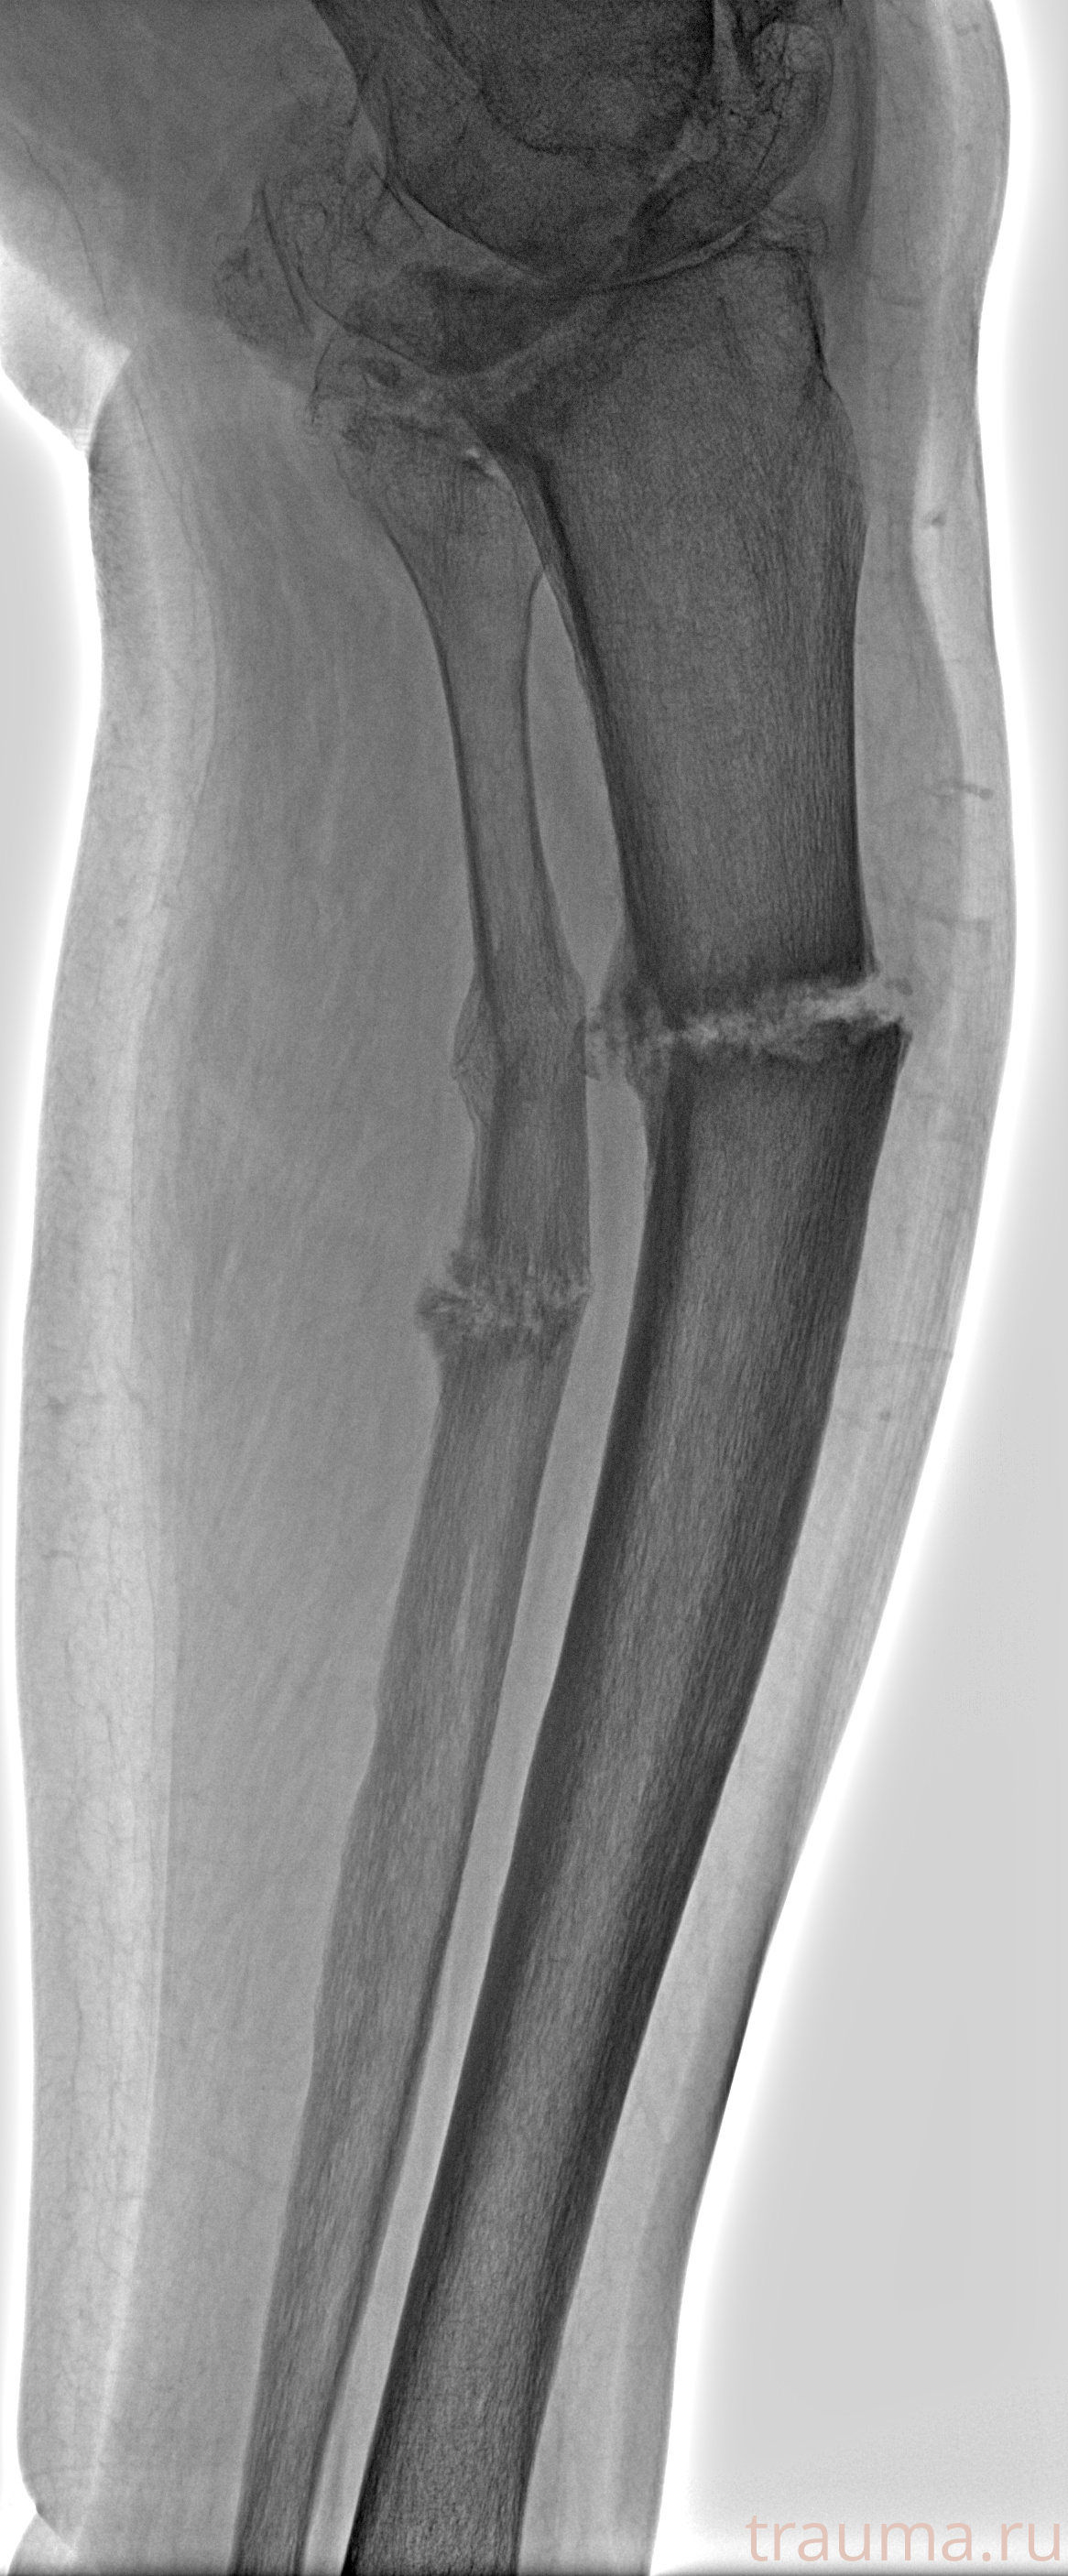

Рентгенограммы

Рентген на дому: по вашему адресу приезжает врач-рентгенолог, травматолог-ортопед с мобильным рентгеновским аппаратом, проводит диагностику травмы или заболевания, делает необходимые рентгенограммы, дает рекомендации по дальнейшему лечению. Получить качественные снимки в домашних условиях возможно благодаря уникальной методике, разработанной МосРентген Центром для института  Склифосовского